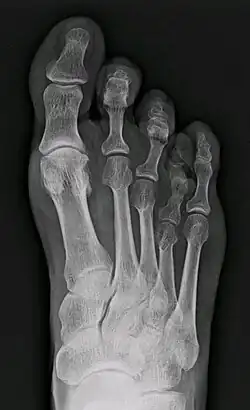

Braquimetatarsia

Braquimetatarsia (del griego brachys, corto, y metatarsia, relativo al metatarso) o metatarso hipoplásico es una condición médica en la cual existe uno o más metatarsos anormalmente cortos.[1] El tipo más común de braquimetatarsia es la que afecta al primer metatarsiano. Esta es conocida como Pie de Morton

Esta enfermedad puede deberse a un defecto congénito o puede ser adquirida.[1] Generalmente afecta al cuarto metatarso y está presente en ambos pies (braquimetatarsia bilateral). En caso de que el defecto esté presente en más de un dedo se le denomina braquimetapodia.[5] En caso de que el metatarso afectado sea el primero, esta malformación se conoce como síndrome de Morton. Frecuentemente, genera un inconveniente desde el punto de vista estético e incluso causa otros problemas como metatarsalgia, callosidades o dificultad para calzarse. Existen varios procedimientos médicos para tratar esta condición.[1]